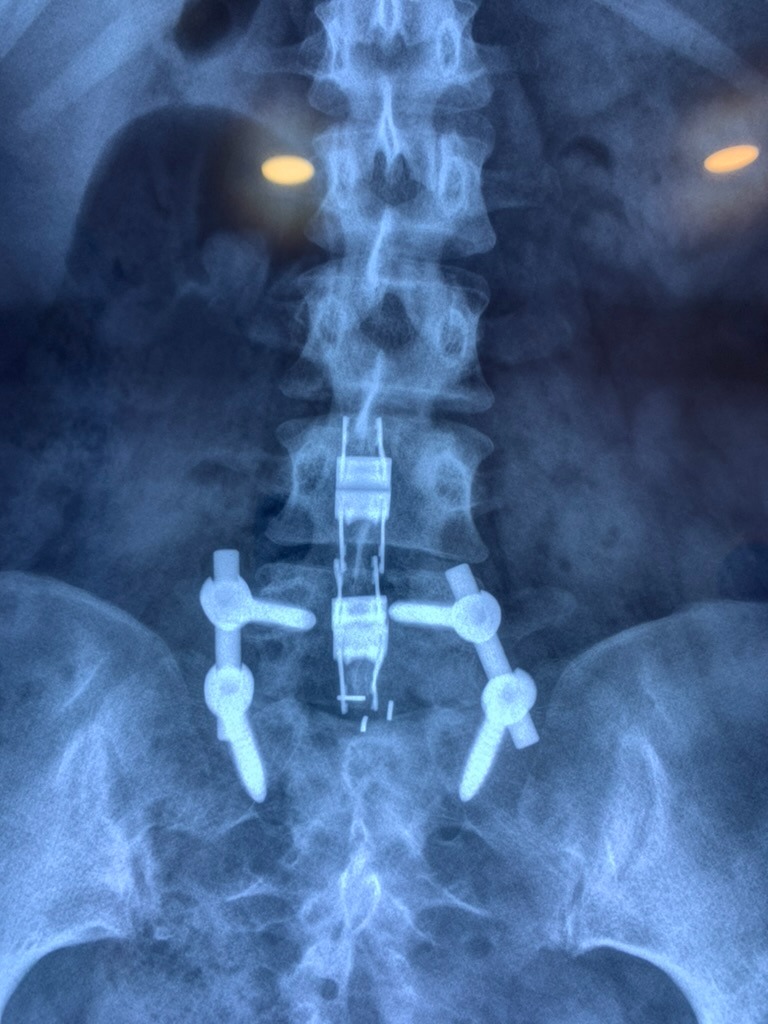

CIRUGIAS

RESULTADOS